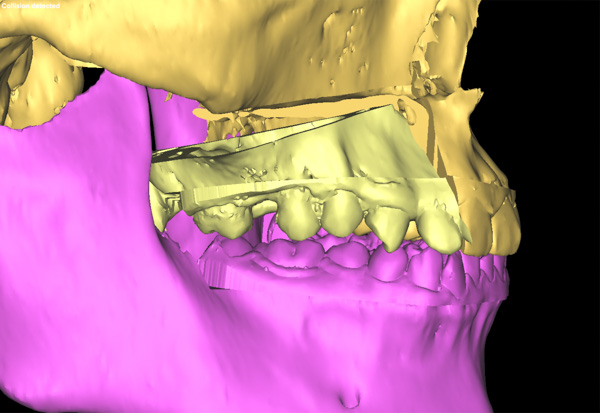

頜面畸形帶給患者心理的痛苦是非常嚴(yán)重的,再加上患者正處在最美好的人生階段,所以手術(shù)只許成功,不許失敗,所有的環(huán)節(jié)必須容不得一絲差錯(cuò)。為了能使上頜骨能精確地移動(dòng),口腔科專家采用了先進(jìn)的3D模擬技術(shù)制作出了咬合導(dǎo)板,在術(shù)前多次模擬重建手術(shù),并向患者展示手術(shù)過程,使手術(shù)過程達(dá)到了最大可能的精準(zhǔn),減輕患者的心理負(fù)擔(dān)。

手術(shù)當(dāng)天,口腔科手術(shù)團(tuán)隊(duì)首先按照術(shù)前設(shè)計(jì)并3D模擬的截骨導(dǎo)板對(duì)右側(cè)上頜骨進(jìn)行精準(zhǔn)分離,按照術(shù)前設(shè)計(jì)的咬合導(dǎo)板精確移動(dòng)上頜骨達(dá)到預(yù)定位點(diǎn),最后精準(zhǔn)的使用堅(jiān)強(qiáng)內(nèi)固定固位。經(jīng)過4個(gè)小時(shí)的努力,完成了正頜手術(shù),待拆除鈦板后即可進(jìn)行咬合關(guān)系和對(duì)稱面型治療。